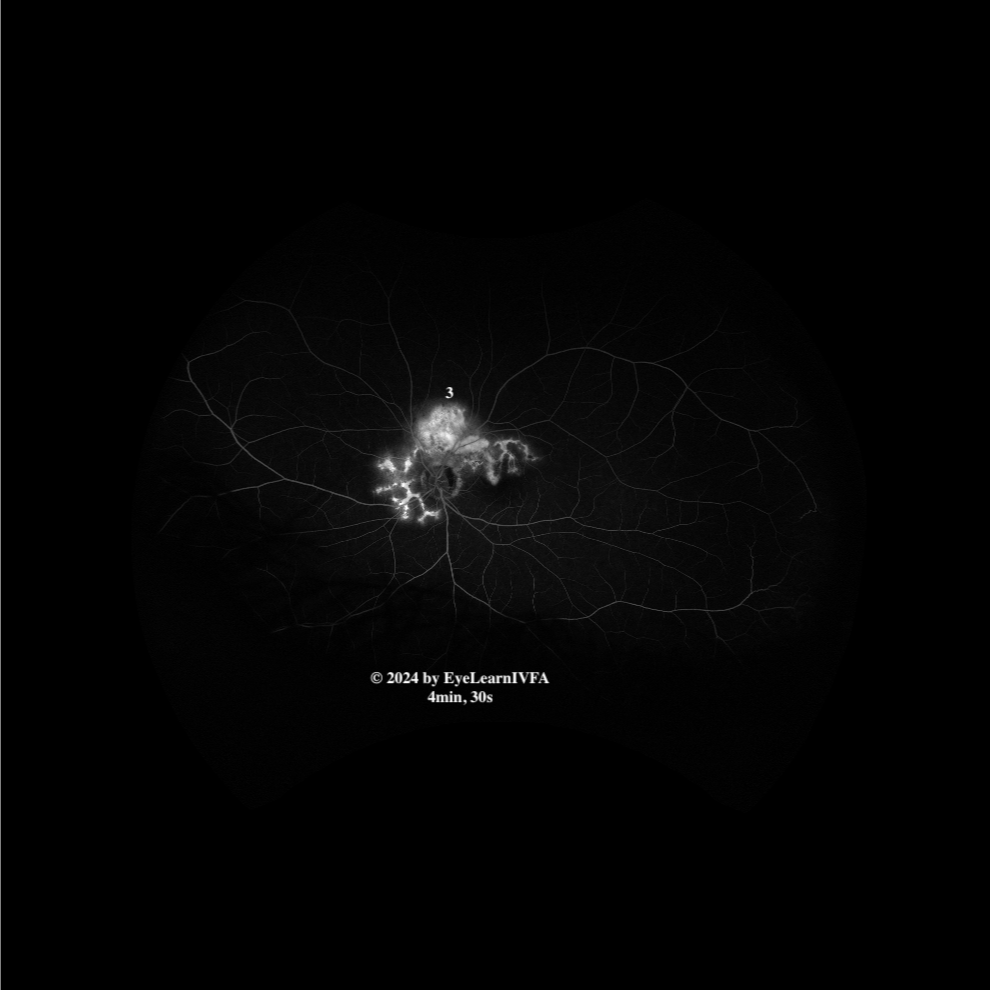

• IVFA at 4 minutes 30 seconds

Late Phase

Key features include:

• Evident serpentine shape.

• Increased intensity and more uniform hyperfluorescence (1) due a mix of leakage and staining over the scar.

• Evidence of late leakage superior to the disc, retinal hemorrhages on fundus photos, and subretinal fluid on OCT points to CNVM in that location (3).